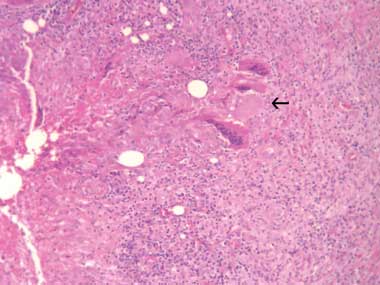

A 31-year-old woman presented with a tender left axillary mass. There was no history of concurrent fevers, sweats or recent illness. She was born in Australia and had not travelled overseas recently. Examination showed a left axillary mass measuring 5 cm in diameter. There was no other lymphadenopathy, no hepatosplenomegaly, nor any breast masses. Aspiration produced 10 mL of purulent fluid. Polymorphs were seen on microscopy but no Mycobacterium spp or other organisms were grown on culture. Histological sections of an excisional biopsy showed nodules of epithelioid histiocytes and giant cells with central necrosis in fibrous stroma, consistent with necrotic granulomatous lymphadenitis (Box, A).

After 6 months of methotrexate treatment the mass recurred. Histological sections from a repeat excisional biopsy revealed the fibrous capsule of a hydatid cyst and multiple scolices. The capsule contained a patchy mixed inflammatory infiltrate and granulomatous reaction with giant cells (Box, B). Hydatid serological testing (by indirect haemagglutination) was positive at a titre of 1 : 640. The presumed exposure was from time spent about 25 years earlier on a farm in rural New South Wales where offal was fed to working dogs.